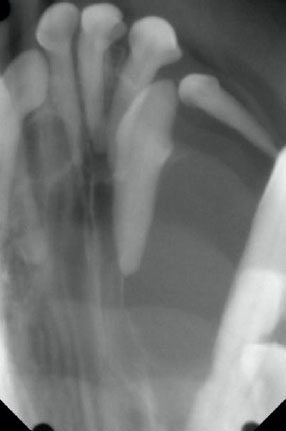

歯科レントゲン画像

ブヨブヨしていた原因は「嚢胞」と呼ばれる液体がたまったものであり、この子の場合は「埋伏歯」が原因で嚢胞が発生していましたので、「歯原性嚢胞」と診断しました。埋伏歯とは、文字通り歯肉の下に埋まっている歯のことで、正常に歯が生えなかった歯のことを言います。この埋伏歯があるかどうかは見た目だけでは分からず、歯科レントゲンや CT 検査などの画像診断を実施しないと診断ができません。また、埋伏歯が存在することで、上記のような歯原性嚢胞を形成することがあり、放っておくと顎の骨を溶かすように大きくなってきます。この子も嚢胞 のせいで顎の骨が溶かされていました。溶けている部分の顎の骨は完全に再生しませんが、これ以上悪化させないために外科手術にて嚢胞の切除と、抜歯処置を実施しました。現在、嚢胞が再発しないか経過を見させていただいております。